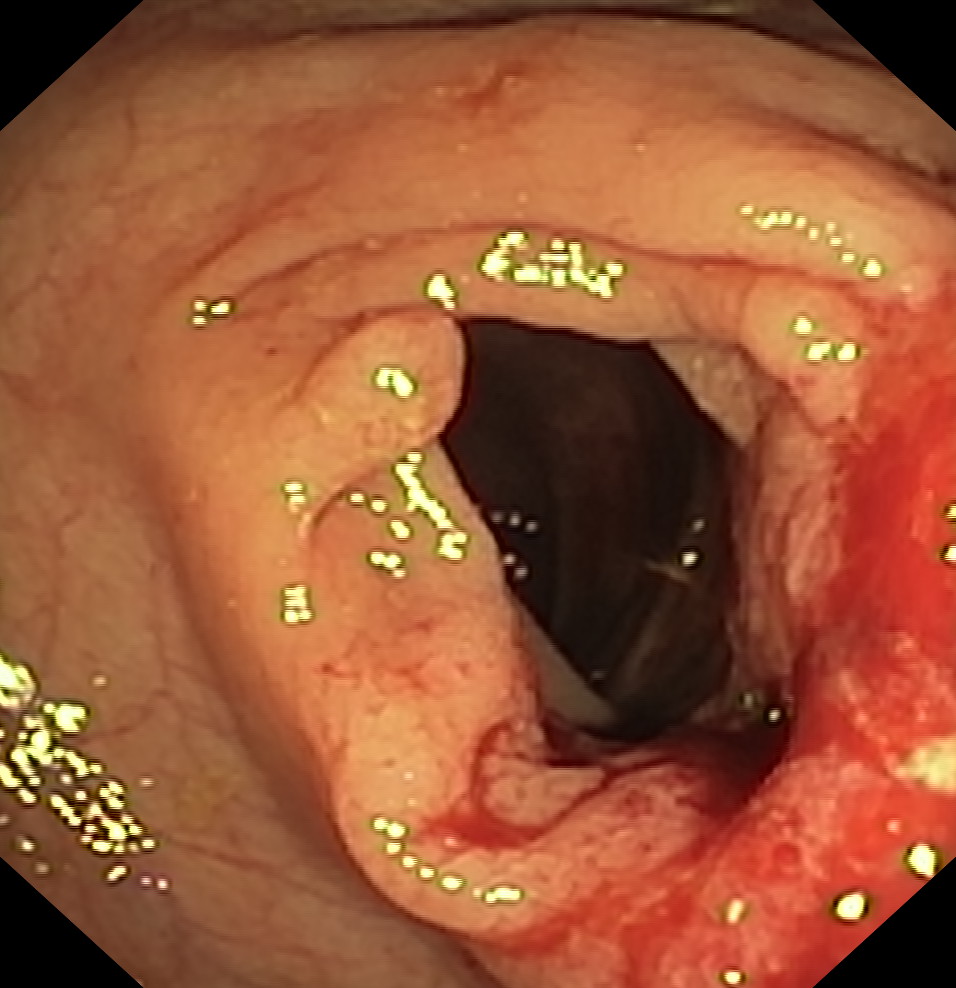

Nowotwory przewodu pokarmowego